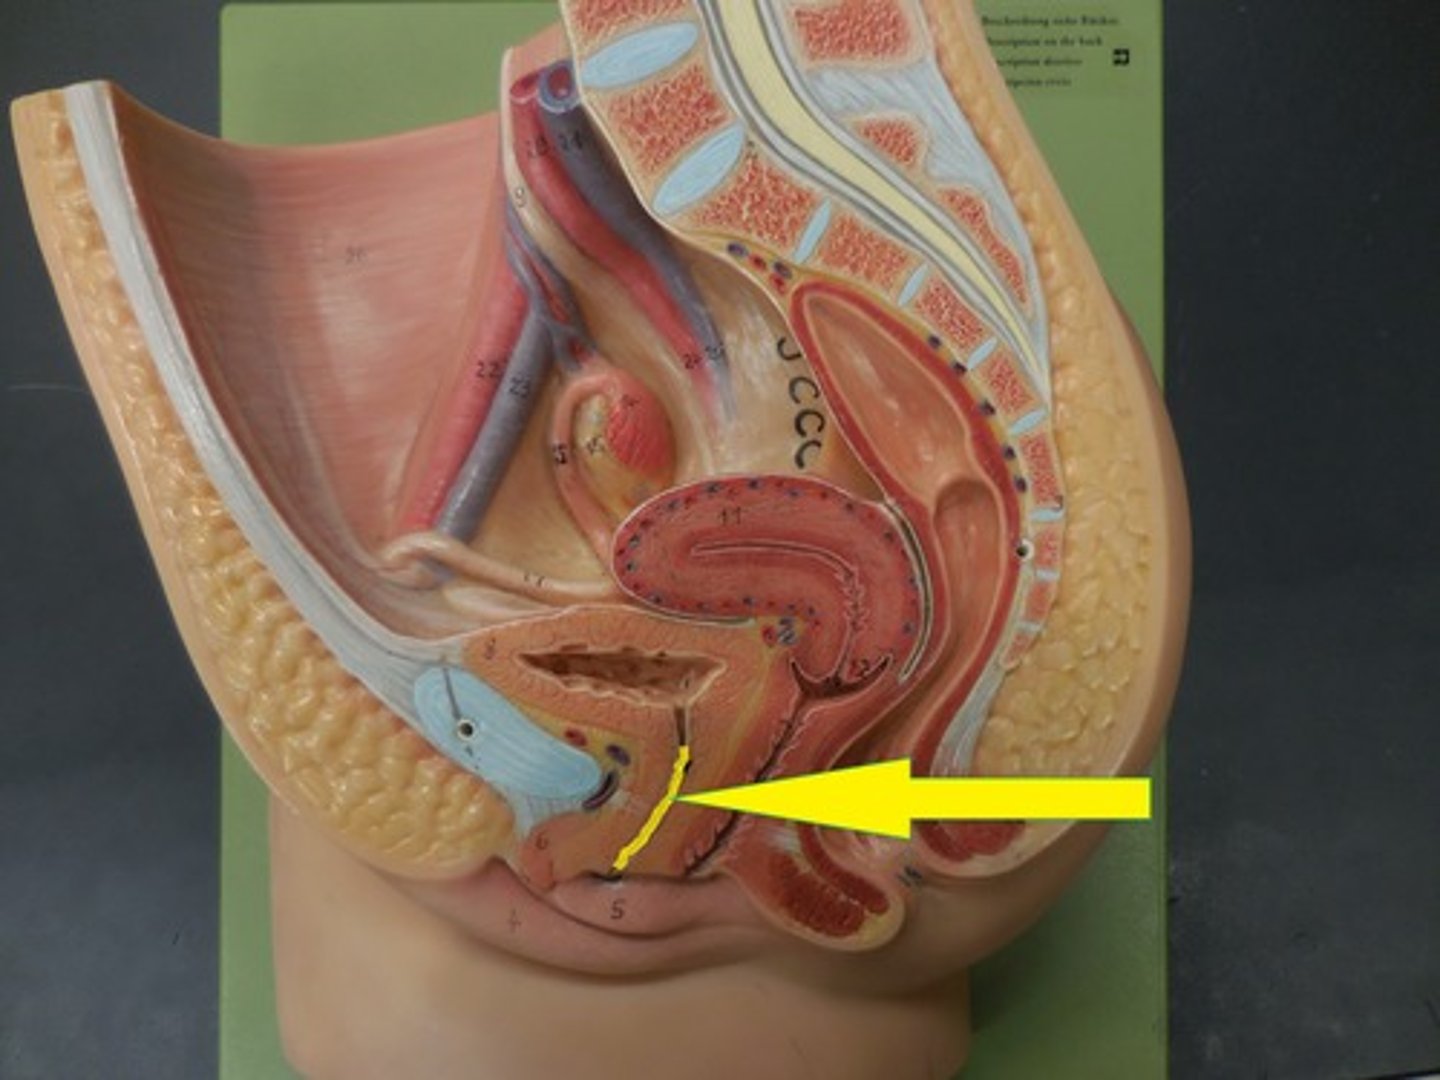

urinary bladder

hollow, muscular sac that holds and stores urine lined with transitional epithelial cells

urethra

tube that carries urine from the bladder to the outside of the body

internal urethral sphincters

involuntary and made of smooth muscle

external urethral sphincters

Voluntary and made of skeletal muscle

detrusor muscle

Smooth muscle that compresses the urinary bladder and expels urine into the urethra.